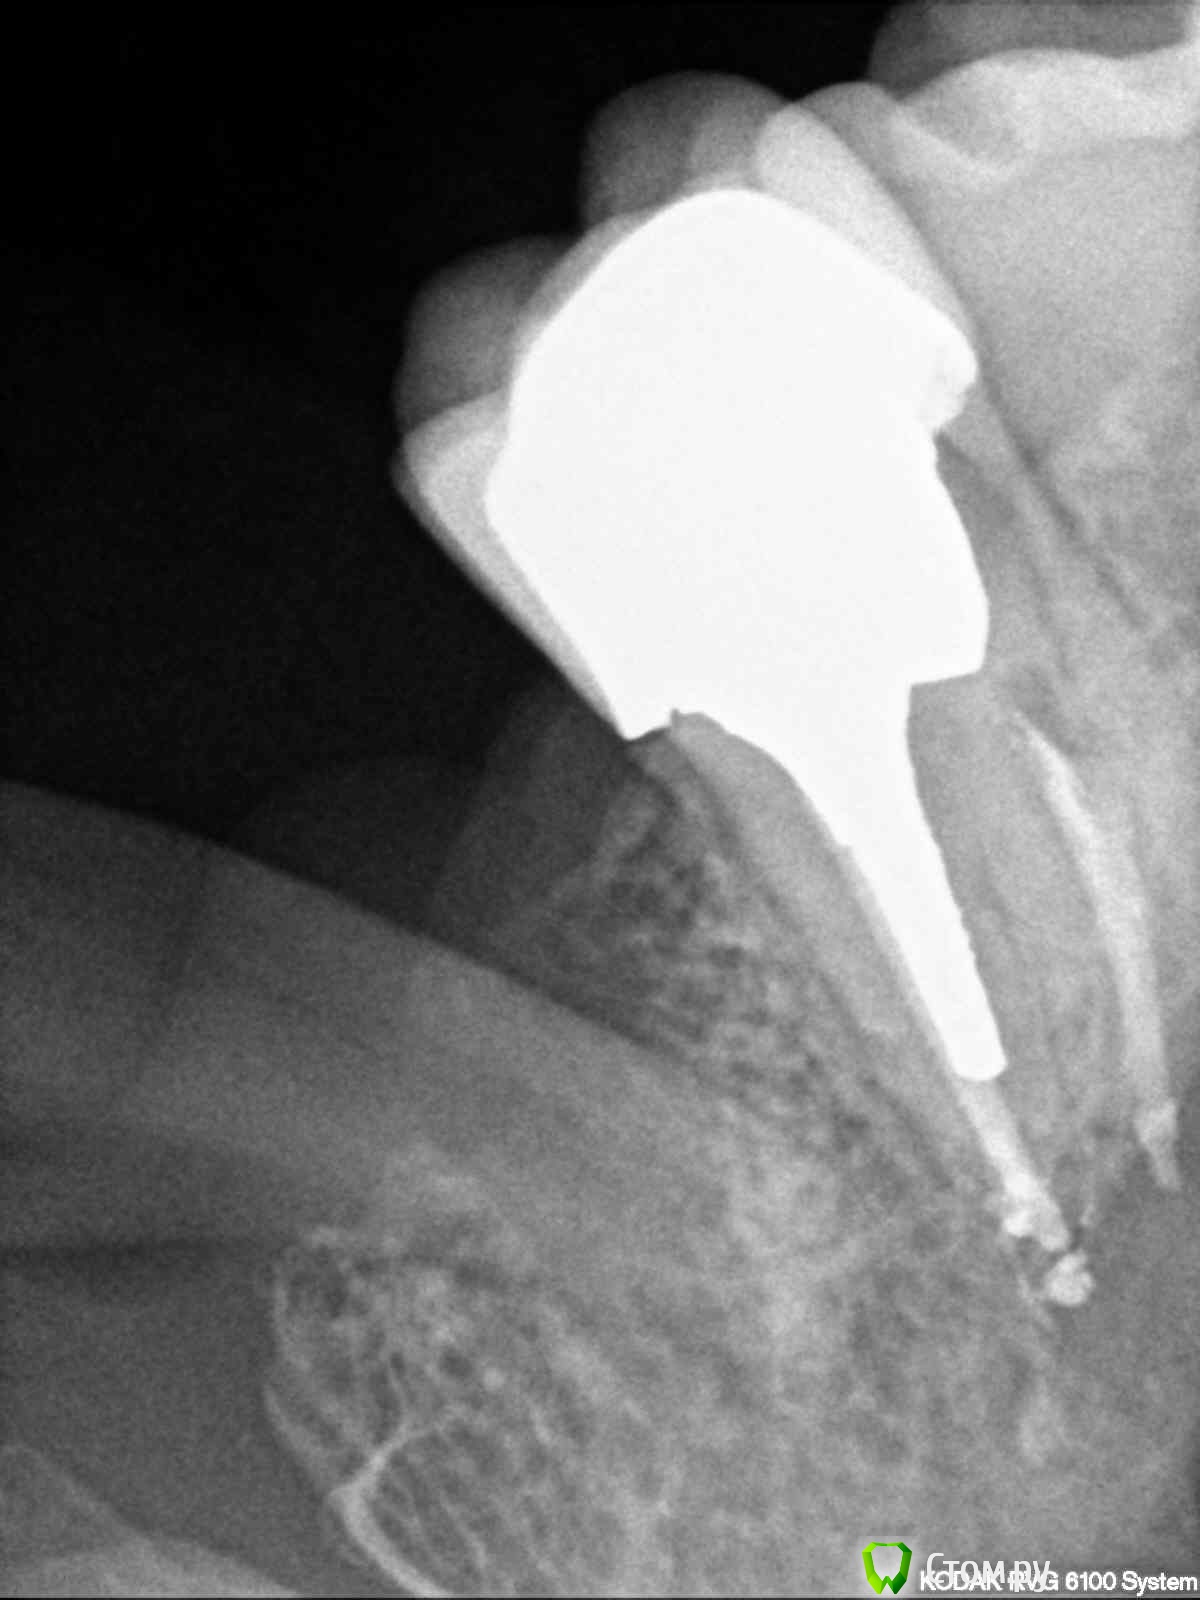

englishlady Опубликовано 6 мая, 2014 Автор Поделиться Опубликовано 6 мая, 2014 Еще один прицельный снимок этого зуба. Есть вариант того, что там пропущен канал?http://s006.radikal.ru/i214/1405/25/67abda2fedab.jpg[/url] Ссылка на комментарий

Гарриевич Опубликовано 6 мая, 2014 Поделиться Опубликовано 6 мая, 2014 Не на одном снимке не увидел третьего канала, разместите кт, посмотрим там Ссылка на комментарий

Scrabble Опубликовано 9 мая, 2014 Поделиться Опубликовано 9 мая, 2014 Вроде сделано неплохо-и пропущенных каналов я не увидела. Если основной проблемой является боль при чистке зубов-советую внимательно посмотреть шейку зуба витального 26-возможно, там есть клиновидный дефект(он может быть очень незначительным) Ссылка на комментарий

Korel Опубликовано 9 мая, 2014 Поделиться Опубликовано 9 мая, 2014 Коллеги, Гм. А какие мысли по поводу 37-38 ? 1 Ссылка на комментарий

M@estro Опубликовано 10 мая, 2014 Поделиться Опубликовано 10 мая, 2014 Коллеги, Гм. А какие мысли по поводу 37-38 ? Как мне видится - оба на удаление. А сверху,как правильно выше отметила коллега,либо клиновидный дефект зуба 2.6, либо - пародонтальная проблема в области 2.6 -2.7 . Пища между этими зубами не застревает ? При прочищении промежутка нитью не кровит? Не разволокняется нить ? Ссылка на комментарий